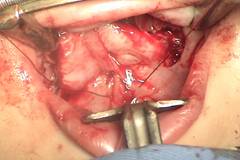

6. Al deslizar el paladar hacia atrás hay un riesgo alto de fístulas en la parte anterior del paladar las cuales son muy difíciles de corregir en el futuro, de hecho ese es el mayor inconveniente de la técnica. Para evitar esas fístulas es fundamental un cierre cuidadoso con colgajos de vomer en la parte más anterior (Fig. 10 y 11).

Figuras 10 y 11: Disección del colgajo de vomer y su sutura en la porción más anterior justo detrás del alvéolo.